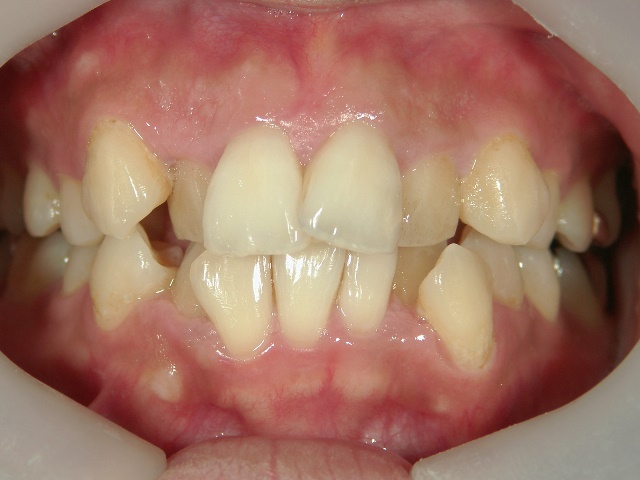

矯正歯科 治療前矯正歯科 治療前

26歳女性 浜松市浜北区在住

治療期間2年

主訴:上下の前歯の歯並びが悪いのが気になる

矯正歯科 治療前 上下左右4番 計4本を抜歯して叢生を改善しました。